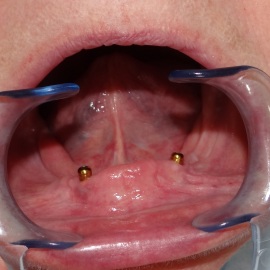

Pacjentka lat 68, prowadzi aktywny tryb życia, dużo podróżuje, przeszkadzały jej klamry widoczne na zębach przy uśmiechu, oraz słaba stabilność protezy, co powodowało dyskomfort przy użytkowaniu.

implanty stomatologiczne implanty stomatologiczne implanty stomatologiczne implanty stomatologiczne